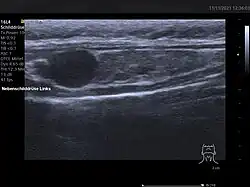

Lokalisationsdiagnostik

Vor einer geplanten Operation können Lokalisation und Größe der betroffenen Nebenschilddrüsenkörperchen durch Sonografie, Szintigrafie mit Technetium-99m-Sestamibi (Nebenschilddrüsenszintigrafie), Computertomographie oder Kernspintomografie dargestellt werden.

Ultraschallbild einer Schilddrüse vom Hund mit Adenom der Nebenschilddrüse

Ultraschallbild einer Schilddrüse vom Hund mit Adenom der Nebenschilddrüse

Die Sensitivität dieser diagnostischen Verfahren ist jedoch begrenzt. Besonders bei komplizierteren Fällen, wie zum Beispiel bei Vorhandensein von mehreren auffälligen Nebenschilddrüsen oder entfernt auftretenden Nebenschilddrüsenadenomen, kann eine zuverlässige Lokalisation aller betroffenen Epithelkörperchen schwierig sein.[60] Neuere bildgebende Verfahren, wie Positronenemissionstomographie (PET) mit speziellen Radiopharmaka wie 68Ga-Trivehexin, können in solchen Fällen eine zuverlässigere Lokalisation ermöglichen,[61] wodurch deren komplette chirurgische Entfernung und damit eine vollständige Heilung des primären Hyperparathyreoidismus wahrscheinlicher wird.